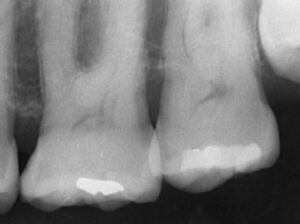

また、歯石の付着位置、歯周病の進行を確認するために、

レントゲン写真を撮って検査します。

矢印の部分に歯石が付いていることがわかります。

クリーニング後のレントゲン写真です。

歯石の付着がなく、歯槽骨(歯を支えている周りの骨)の吸収がおさまっていることを確認します。